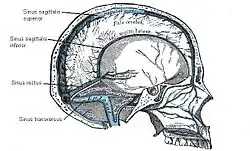

Abflüsse

Das Gehirn besitzt kleine Venolen und Venen wie andere Organe auch, die jedoch unabhängig von den Arterien verlaufen. Sie werden in eine tiefe (Venae profundae cerebri) und eine oberflächliche (Venae superficiales cerebri) Gruppe unterteilt. Die größte Hirnvene ist die nur etwa 1 cm lange Vena magna cerebri (Galeni) unter dem Splenium des Balkens. Das sauerstoffarme Blut wird in anatomisch besonders gebauten Hirnblutleitern, den Sinus durae matris gesammelt: Dabei handelt es sich um Duplikaturen der harten Hirnhaut, die auf der Innenseite mit Endothel ausgekleidet sind. Die Sinus bilden ein miteinander verbundenes System und münden schließlich in die inneren Drosselvenen.